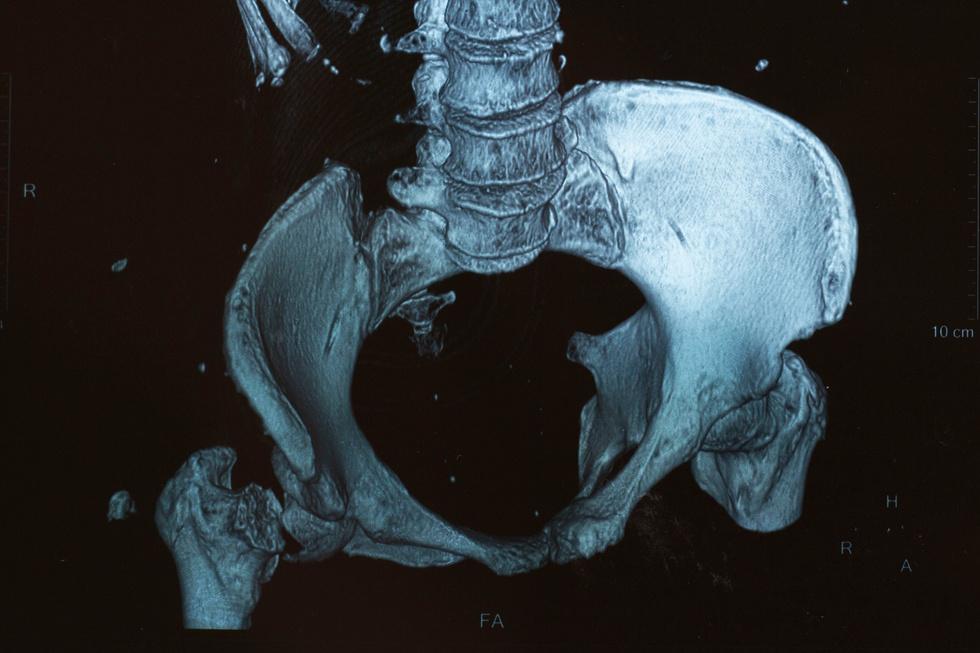

Six months after a hip fracture, only 15 percent of patients can walk across a room unaided.

Every year, of nearly 300,000 hip fracture patients, one-quarter end up in nursing homes, and half never regain previous function.

From these alarming statistics, we can clearly see that osteoporosis and osteopenia are serious public health threats.